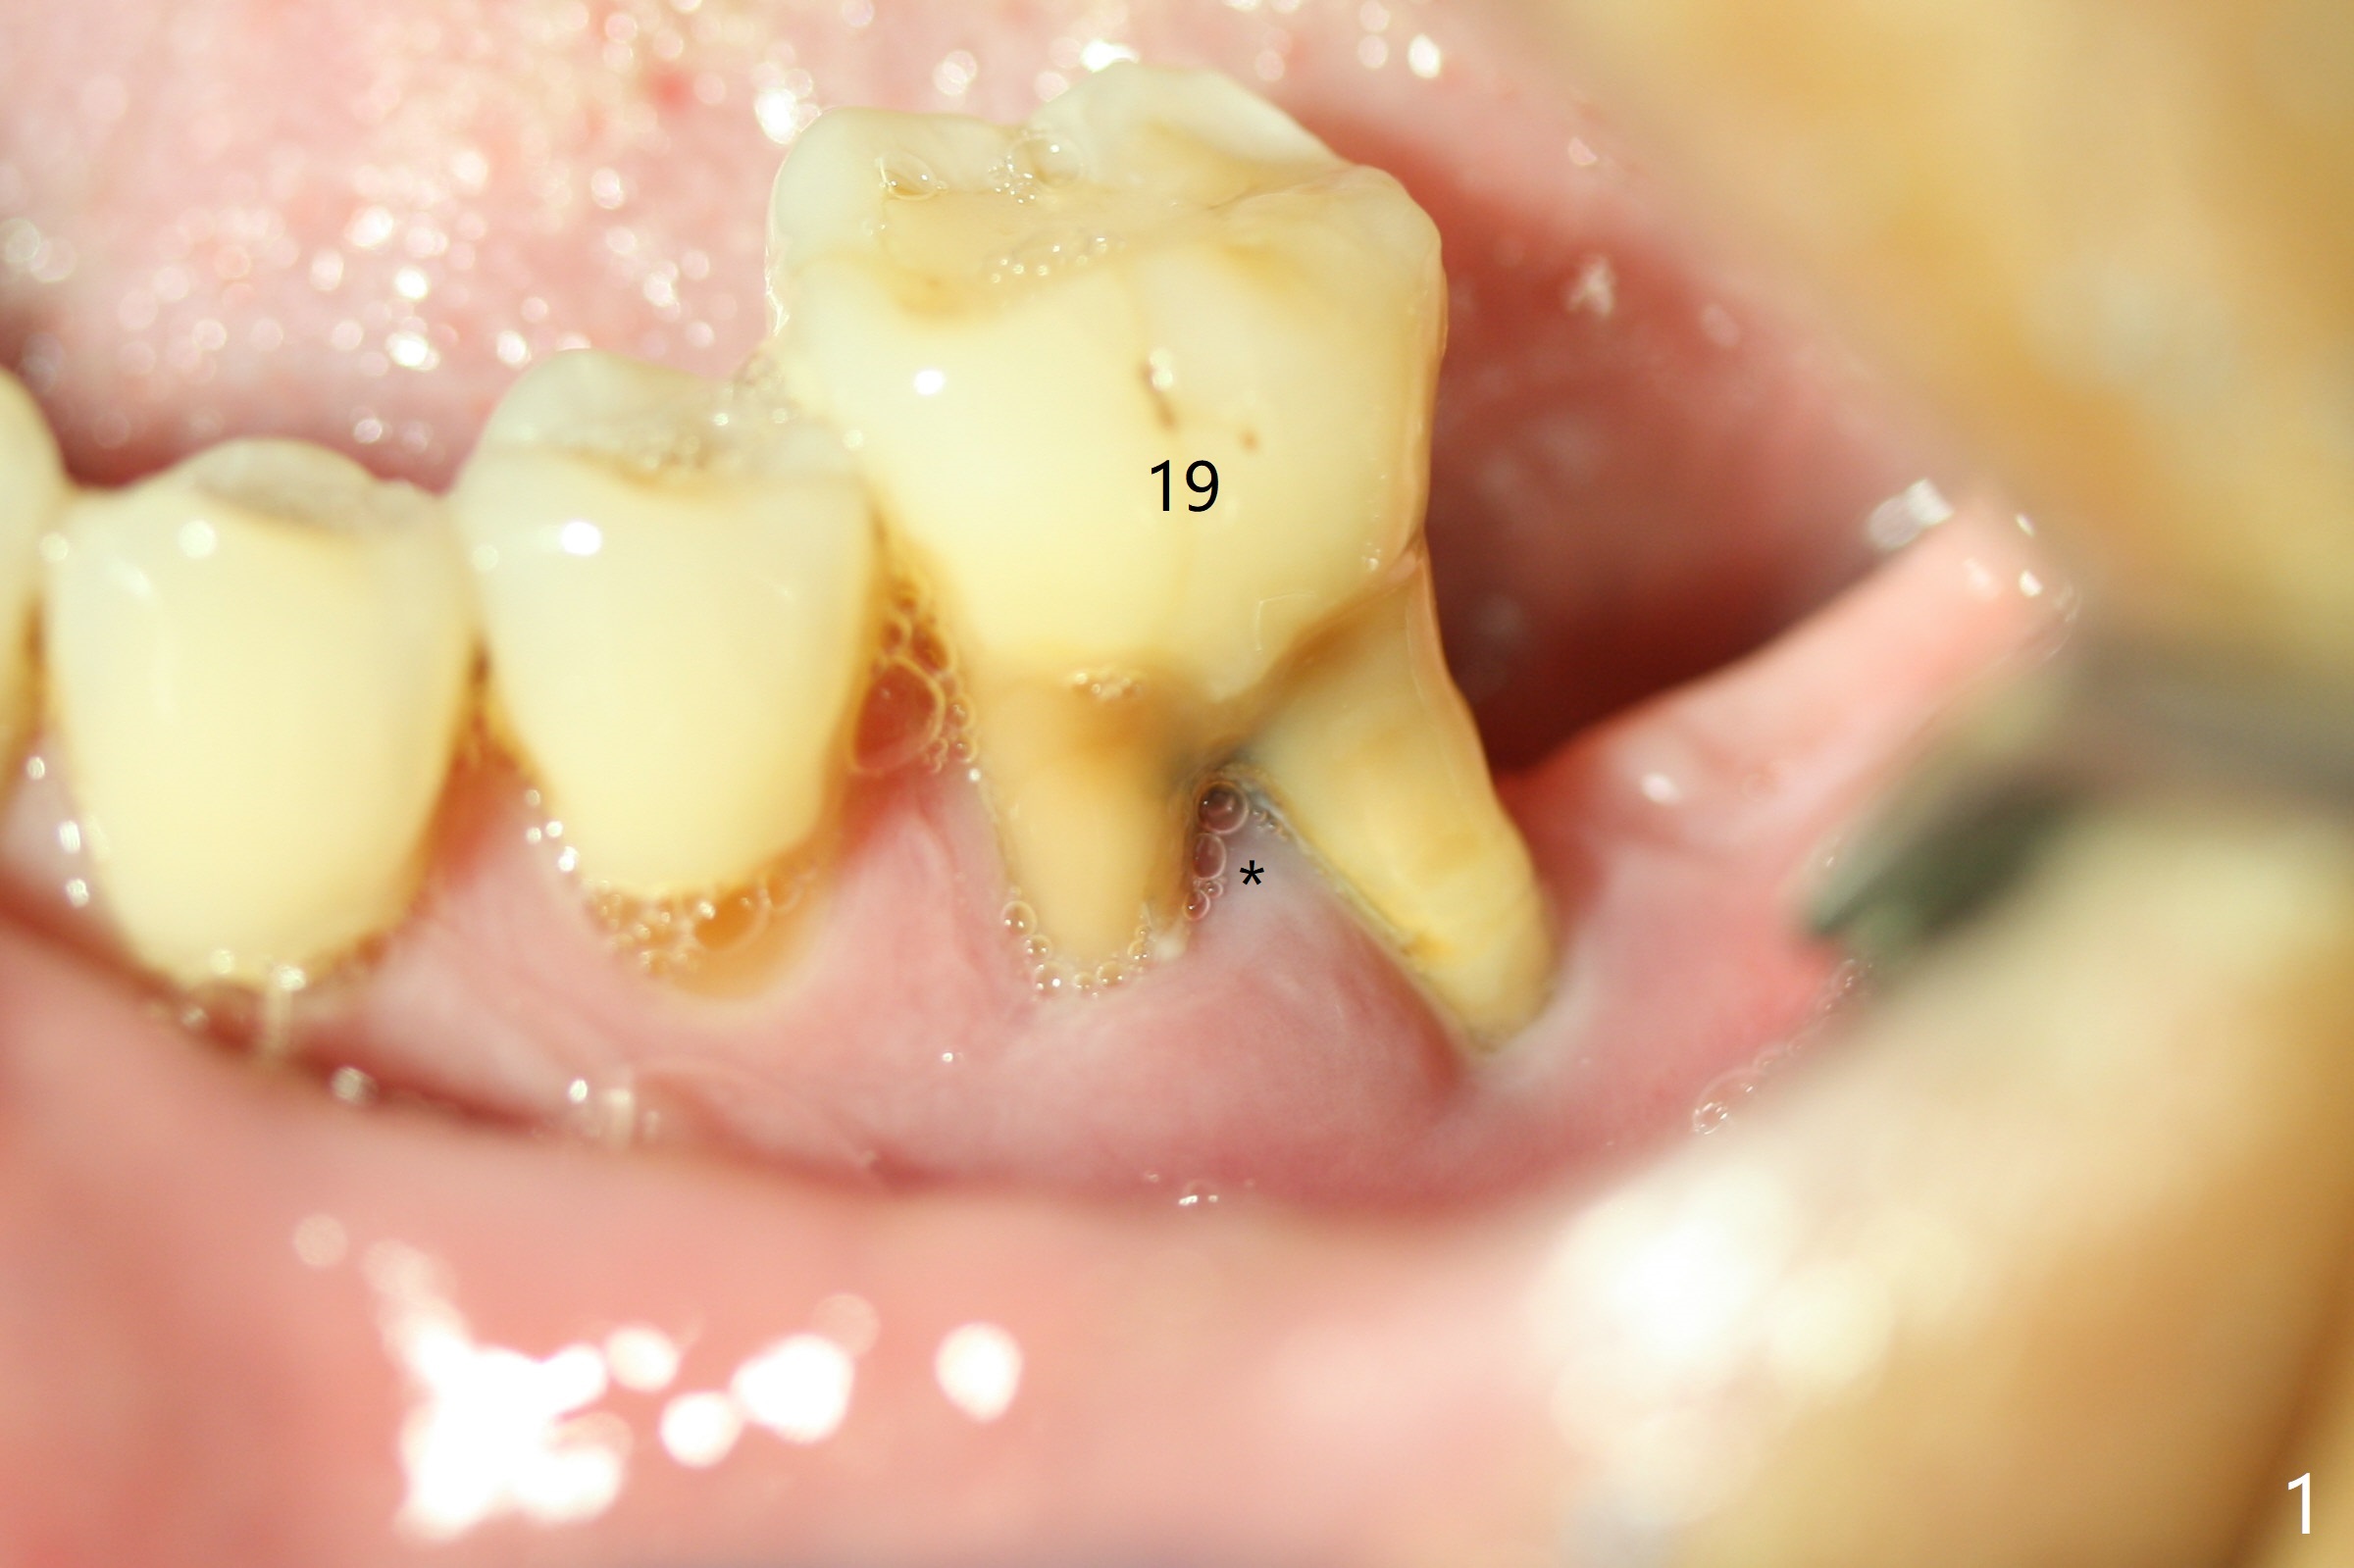

When the patient returns for #19 extraction (Fig.1), there is no 5x10 mm implant available. In fact the smaller one (4.5x10 mm) is able to achieve insertion torque >60 Ncm with more room for autogenous bone/allograft horizontally (Fig.2 *). After insertion of a definitive abutment (6.5x5.5(4) mm), more allograft is placed coronally (Fig.3 *). The gingiva that was between the mesial and distal roots before extraction (Fig.1 *) is transferred distal (Fig.4.5 *). An immediate provisional (Fig.6 P) is fabricated to close the socket opening, followed by periodontal dressing (data not shown). The latter is partially detached 2 weeks postop (Fig.7 D). When it is removed, some of possibly collagen plug is exposed distobuccally (Fig.8). When the plug is removed, some of the bone graft (Fig.9 *) is exposed distal to the provisional (P). New periodontal dressing is applied to keep the exposed graft in place. There is no apparent thread exposure 4 months postop (Fig.10). The abutment is loose 4 months post cementation, probably related to unfavorable crown/implant ratio; but when the abutment is retightened, there is a gap between it and the implant (Fig. 11 >). After relieving the proximal contact of the crown, the abutment is retightened one more time with the same gap (Fig.12 >). In fact the latter is present previously. A narrower abutment with longer cuff appears to be completely seated, probably avoiding contact with the regenerated crestal bone (Fig.13 *). If the new crown gets loose, bury a driver inside the abutment.